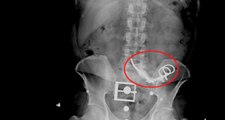

Meksikalı sosyal medya fenomeni ve bekar anne Denisse Reyes, yetkisiz bir cerrah tarafından gerçekleştirilen liposuction ameliyatı sonrasında hayatını kaybetti. 27 yaşındaki Reyes'in sağlık durumu, operasyon sonrasında hızla kötüleşmiş ve üç gün sonra kalp durması sonucu yaşamını yitirmiştir.

Bekar anne ve sevilen sosyal medya fenomeni Denisse Reyes, Meksika'da geçirdiği yağ aldırma ameliyatının ardından trajik bir şekilde hayatını kaybetti.27 yaşındaki fenomenin sağlık durumu, Tuxtla Gutiérrez'deki San Pablo Tıp Kliniği'nde yetkisiz bir cerrah tarafından yapılan operasyonun ardından hızla kötüleşti. Üç gün sonra kalp durması sonucu hayatını kaybetti.Ailesinden yapılan açıklamaya göre, 26 Ocak'ta Dr. Orlando Gamboa tarafından yapılan ameliyatta, Denisse'in damar içi ilaçlara karşı kötü tepki verdiği belirtildi.Denisse'in amcası Ammao Rodríguez, Daily Mail'e yaptığı açıklamada, "Yeğenim ameliyattan sonra rahatsızlanmaya başladı ve kalbi durdu.